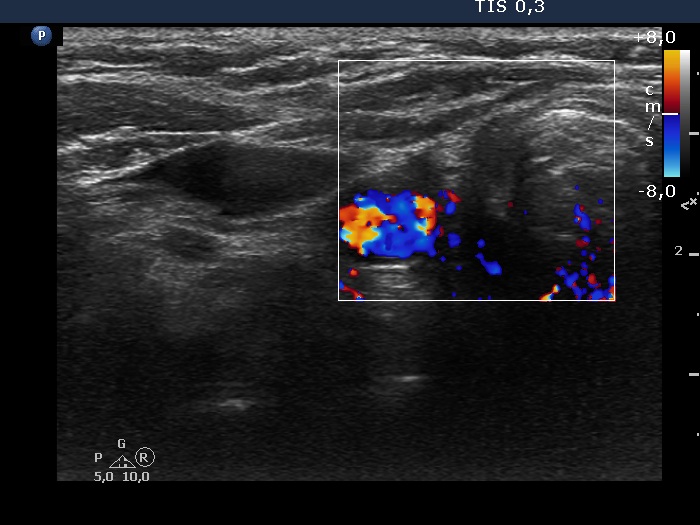

Right lobe, longitudinal scan

Right lobe, transverse scan, color Doppler mode. There is no vascularization in the thyroid bed.